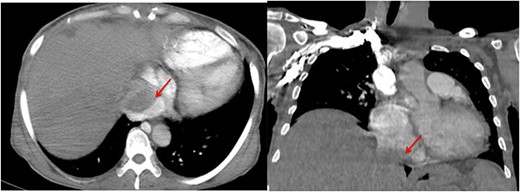

The pathological and immunohistochemical examination suggested a smooth muscle mesenchymal tumor without signs of malignancy, raising the possibility of disseminated intravascular leiomyomatosis or a BML (Figs 4 and 5). The thoracic computed tomography (CT) indicated the presence of a mass in the inferior vena cava extending into the right atrium. Magnetic resonance imaging (MRI) confirmed uterine leiomyomatosis (Fig. 3). This explains the origin of the mass in the right atrium.

Angio-CT thoracic images reveal the presence of a mass in the inferior vena cava extending into the right atrium (arrow).

Exploring the inferior vena cava at its intra-abdominal portion was difficult because it was compressed by the uterine mass (Fig. 2). Following discussions and collaboration among vascular surgery, gynecology, anesthesiology, cardiothoracic surgery, and intensive care, the diagnosis of intravascular leiomyomatosis was confirmed.

CT and MRI are crucial for determining the size and shape of the uterus (Figs 2 and 3), confirming the myometrial origin of the mass, and specifying the extent of vascular involvement. This classification distinguishes four grades [1]: